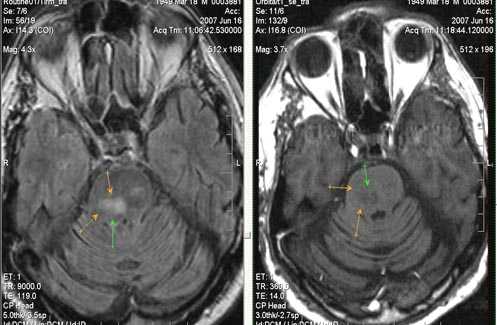

Бассейн кровоснабжения левой верхней мозжечковой артерии, острая стадия НМК.

Ишемическое ОНМК, ствол мозга (подострый период)

Одно из преимуществ МРТ в оценке последствий инсульта - возможность визуализировать нисходящую Валлеровскую дегенерацию аксонов в стволе мозга и кортико-спинальном тракте на стороне поражения.